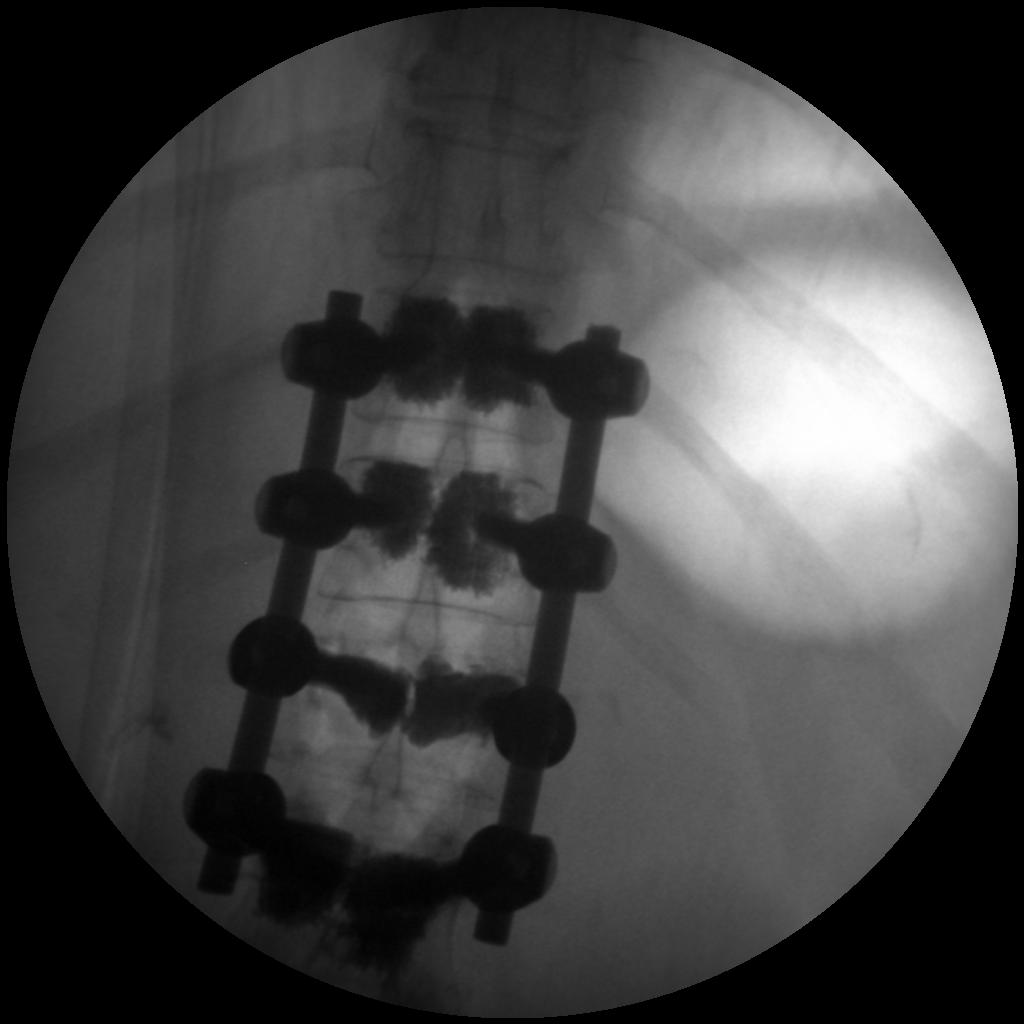

High-quality imaging

Skan-C uses advanced imaging technology, such as pulsed fluoroscopy and digital subtraction angiography, to provide highly detailed images of the affected area. This allows doctors to perform procedures with increased precision and accuracy, and better patient outcome

Clinical Evidence

Skan-C is a great C-arm for neurology treatments for several reasons